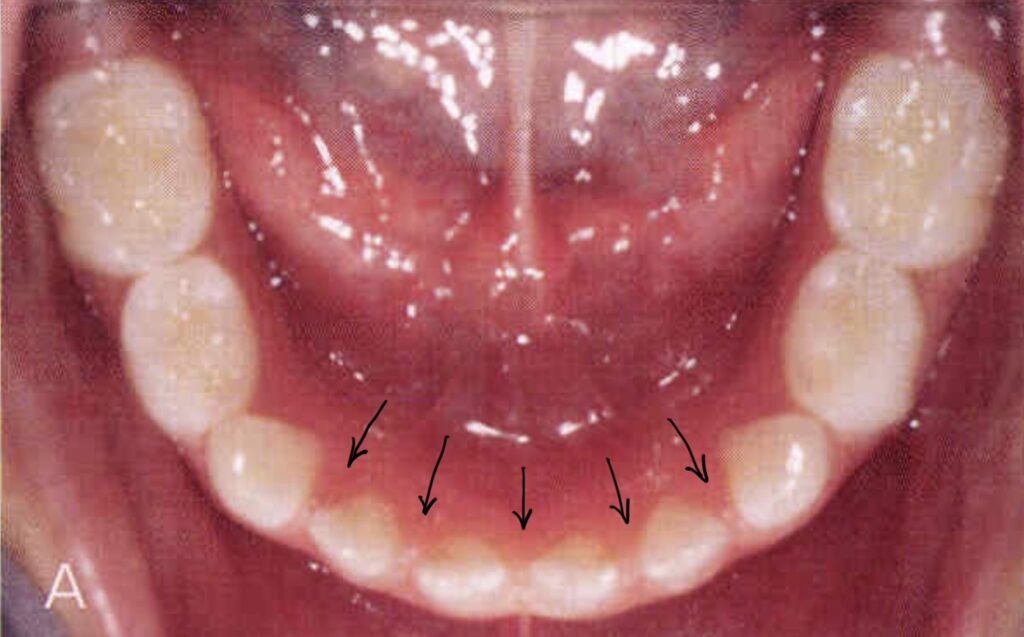

子どものすきっ歯とは、専門用語で「空隙歯列(くうげきしれつ)」と呼ばれ、歯と歯の間に本来あるべき接触がなく、隙間が空いている状態を指します。

特に上の前歯の真ん中に隙間がある場合は「正中離開(せいちゅうりかい)」と呼ばれます。

乳歯の時期であれば、すきっ歯は決して珍しいことではありません。むしろ「霊長空隙(れいちょうくうげき)」「発育空隙(はついくくうげき)」といって、後から生えてくる大きな永久歯のためのスペースとして、隙間がある方が正常な場合もあります。

状態としては、前歯の真ん中だけが数ミリ開いているケースから、歯列全体にパラパラと隙間があるケースまで様々です。

また、上の前歯の付け根あたりに「正中過剰歯」という余分な歯が骨の中に埋まっていると、それが邪魔をして永久歯の前歯が寄り添えず、パカッと開いてしまうケースも非常に多く見られます。

この筋の付着位置が低すぎたり、筋自体が太すぎたりすると、前歯の真ん中に入り込んでしまい、物理的に前歯が閉じるのを邪魔してしまいます。